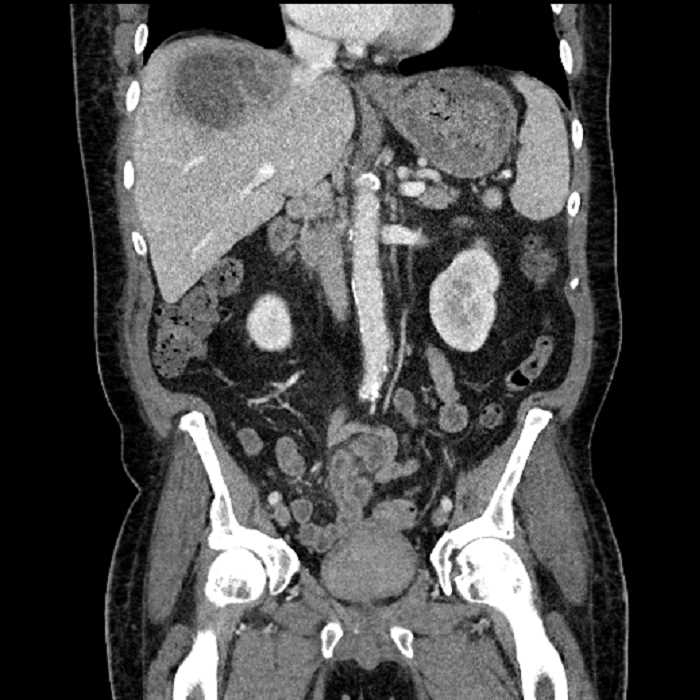

Age: 63

Sex: Male

Indication: Abdominal pain

• Large fluid density structure in hepatic segments 7 and 8 measuring 10 x 7 x 7 cm with internal septation and circumferential ill-defined low density compatible with edema

• Peripherally enhancing subcapsular collections along the anterior margin of the left hepatic lobe measuring 3 x 1 cm and 2 x 1 cm

• Clearly marginated fluid density structure in segment 7 and several other scattered tiny hypodensities, which likely represent cysts

• Hepatic abscess

Acute sigmoid diverticulitis complicated by a small contained perforation and a large abscess in the right hepatic lobe. Additional small subcapsular abscesses along the anterior margin of the left hepatic lobe.

Additionally, loss of the normal fat plane between the peridiverticular collection and adjacent thickened loops of small bowel raises the potential for an enterocolonic fistula.

Hepatic abscess showing the double target sign with low density internally surrounded by a thin inner enhancing rim (red arrow) and ill-defined outer low density rim (yellow arrow). Blue arrow indicates an internal septation. Red arrows: additional smaller subcapsular abscesses. Red arrow: focal contained perforation associated with diverticulitis.